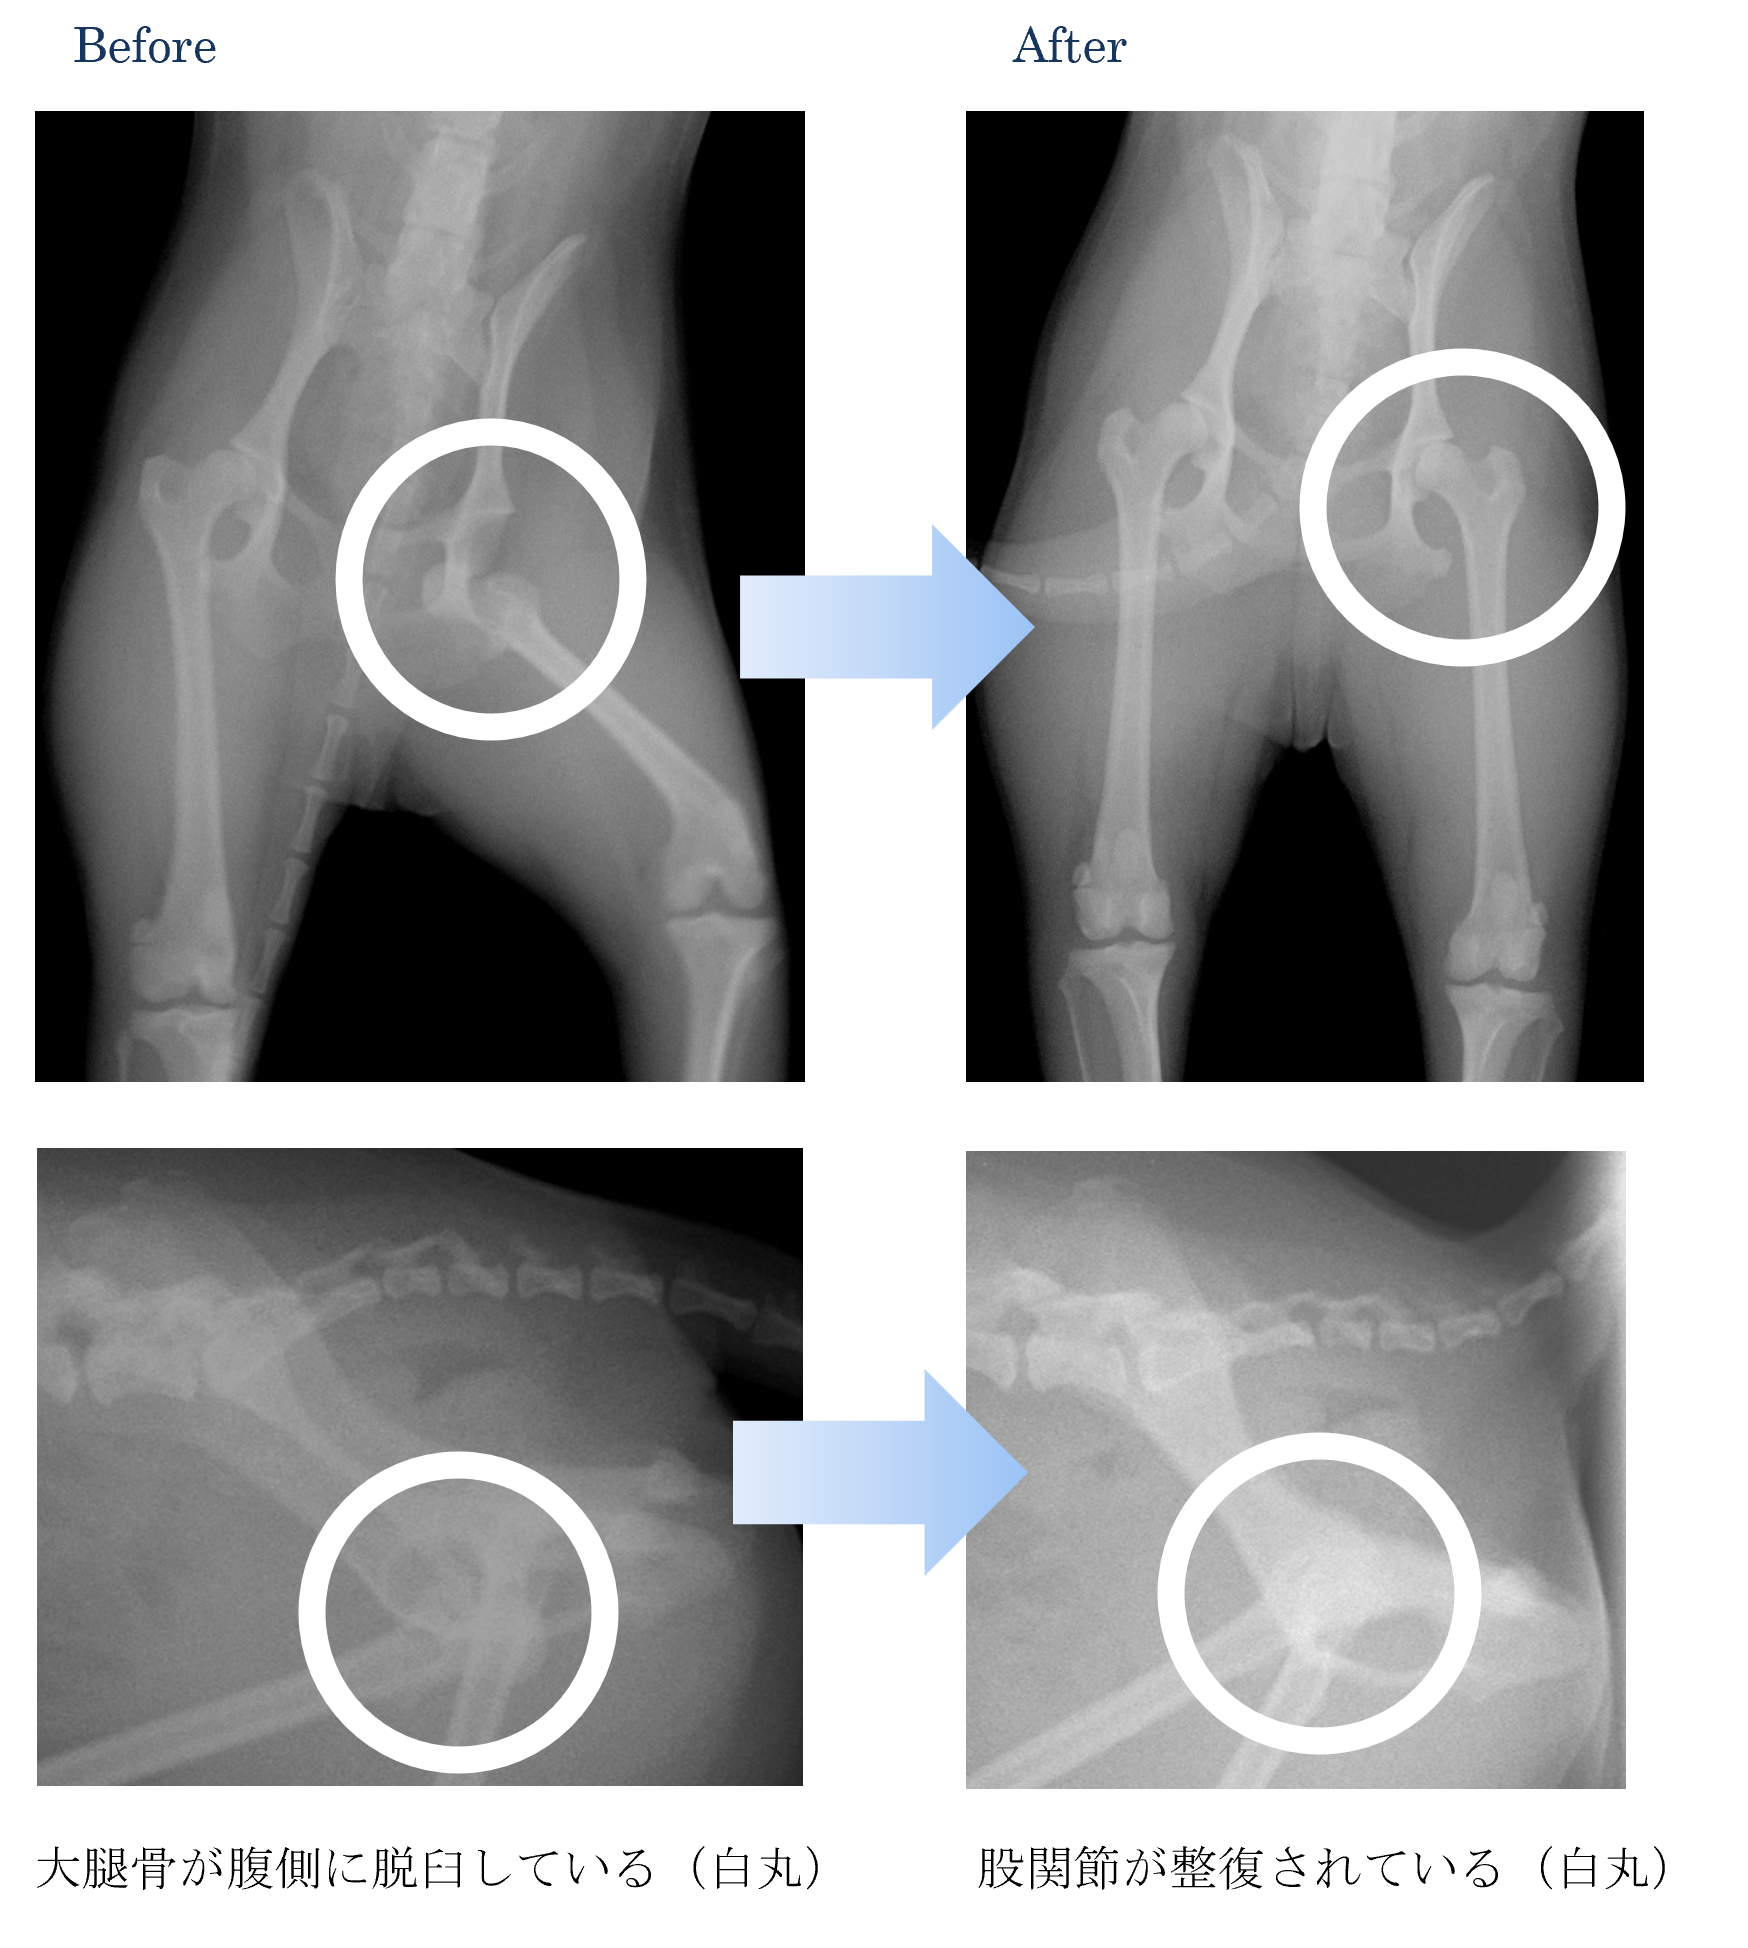

他の犬ちゃんが飛び乗ってしまった時に痛がってから後ろ足を挙げている。

各種検査より、股関節脱臼(腹側)と診断しました。

ご家族と相談から、膝蓋骨脱臼を整復して外固定(包帯)を実施することになりました。

股関節が安定したころに外固定を外しました。

手術後は以前と同じように走ったり遊んだりすることができるようになりました。